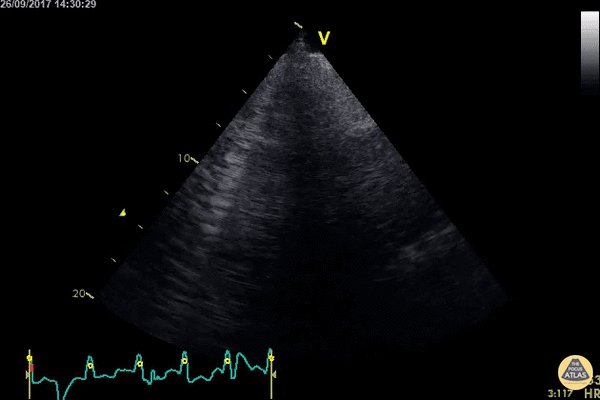

00 - Normal parasternal long-axis (PLAX) view

01 - LV dysfunction in PLAX

02 - RV dysfunction in PLAX

03 - Tamponade in PLAX